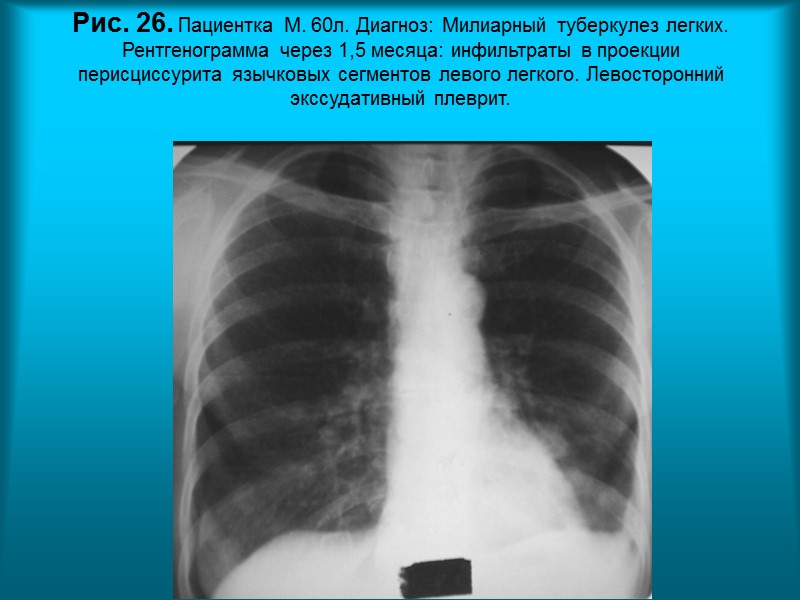

Н.С. Воротынцева. С.С. Гольев Рентгенопульмонология Рис.25. Пациентка М. 60л. Диагноз: Милиарный туберкулез легких на фоне перенесенного левостороннего перисциссурита и плеврита.

Н.С. Воротынцева. С.С. Гольев Рентгенопульмонология Рис. 26. Пациентка М. 60л. Диагноз: Милиарный туберкулез легких. Рентгенограмма через 1,5 месяца: инфильтраты в проекции перисциссурита язычковых сегментов левого легкого. Левосторонний экссудативный плеврит.